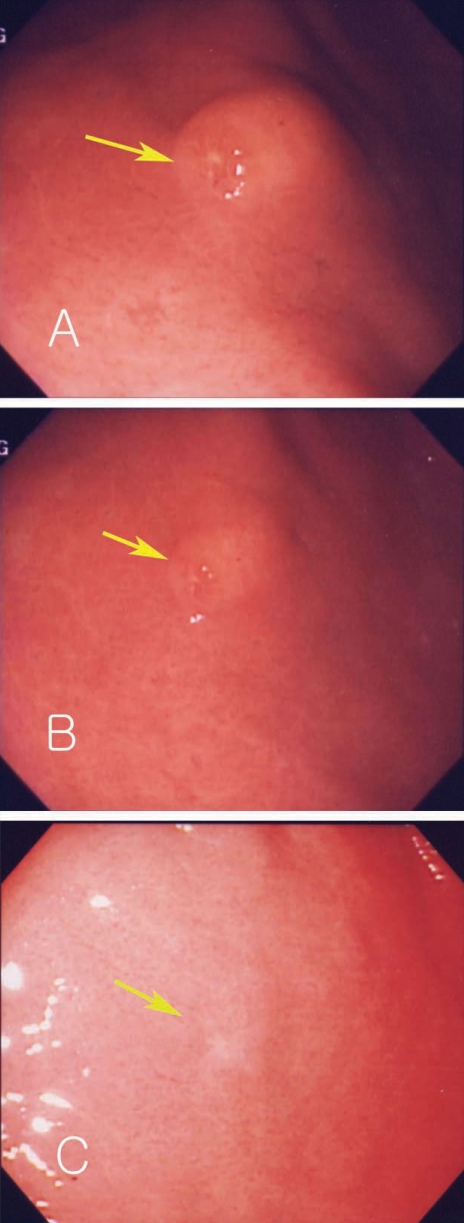

Fig. 3

Endoscopic findings of Case 2, show a single submucosal tumor-like lesion with an eccentric erosion in the antrum (arrow) (A). The size of the same lesion decreased after 3 mo (B, C).

A 45-year-old man complained of abdominal pain and loose stools which had persisted 3 to 4 times a day but without bloody or mucoid diarrhea, fever, or myalgia. His medical history showed no evidence of any specific disease. Physical examination showed stable vital signs. Abdominal epigastric tenderness was presented without rebound tenderness. We prescribed antacids and mucosal protecting agents for conservative management and gastric endoscopy was performed. Endoscopy showed a submucosal tumor-like lesion with yellowish surface at the proximal part of the antrum in the stomach. Some lesions showed erosions and hard surface consistency (Fig. 3A). A biopsy finding revealed severe gastritis with eosinophilic infiltrations. History taking revealed eating of raw sea eels and ascidians before the symptom onset. Laboratory data showed white blood cell count of 13,920 × 103/µL, and eosinophils 12.8%. Considering his history, laboratory test results, and endoscopic and pathologic findings, a submucosal tumor-like lesion caused by anisakid larval infection was suspected. We prescribed albendazole and 2 months later performed a follow-up endoscopy which showed a decrease in size and scarring corresponding to the location of the previous submucosal lesion at the anterior wall of the antrum (Figs. 3B, 3C). A biopsy showed reduced eosinophilic infiltrations and laboratory test showed that white blood cell counts reduced to 7,700 × 103/µL, with eosinophils at 9.6%.